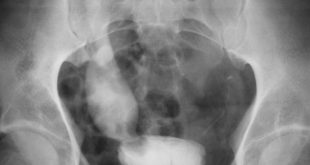

Un nuevo estudio asegura que el cáncer de vejiga es ahora el cuarto cáncer más común entre la población mexicana. El cáncer de vejiga se ha convertido en el cuarto cáncer más común en la población mexicana. Al parecer, este cáncer poco estudiado es cuatro veces más frecuente entre hombres …